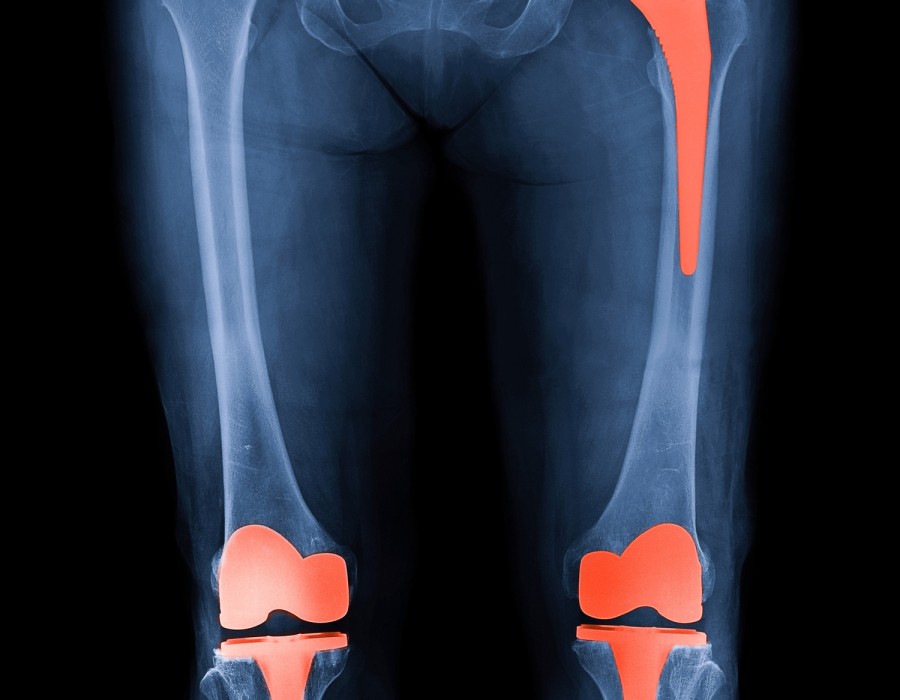

2. Knee Replacements: Knee replacements tend to last slightly longer than hip replacements, with an average lifespan of 20–25 years. Again, this can vary based on individual factors.

It’s important to note that while joint replacements are designed to be durable, they may eventually wear out or loosen over time.Orthopedic Surgeon in Jagatpura, Jaipur Factors such as the patient’s age, weight, activity level, and any complications (like infection or bone loss) can influence how long the implant lasts.

Regular follow-up with the orthopedic surgeon is crucial to monitor the condition of the joint replacement and detect any signs of wear or potential problems early. If a joint replacement does wear out or become problematic, revision surgery (replacing the implant) may be necessary to restore function and alleviate pain.